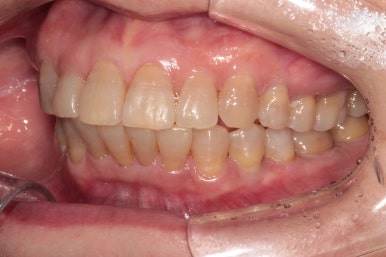

앞니가 좀 삐뚤어져 있었습니다.

보통 아래 앞니보다는 위 앞니가 삐뚤빼뚤 할 때 상담차 오시곤 하는데요,

아무래도 환자의 대부분이 성인이다보니 그런 것 같아요.

위에 보이는 사진은 교정장치를 붙이고 불과 4개월 후 입니다!

생각보다 위턱 앞니가 빨리 가지런해 진 것을 확인할 수 있습니다.

아래 앞니만 조금 더 가지런해지면... 될 것 같은 느낌이네요.